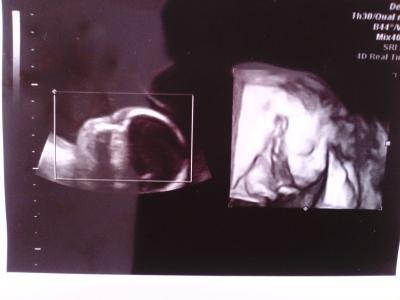

nachdem ja jeder sagte ich würde bestimmt ein mädchen bekommen wegen den annemärchen weil alles auf ein mädchen gepasst hatte,unter anderem hab ich ganz schlimme akne im gesicht auf dekolte und rücken,fettige haare nach einem tag und schuppen alles was ich vorher nicht hatte. Hatte ich gestern eeeeendlich mein erstes outing von meinem arzt Da ist das linke bein.......da das rechte bein......und das hier in der mitte ist sein rechtes bein

Herzlichen glückwunsch es ist ein Junge

und mein arzt hat mir kostenlos ein 4D bild gemacht